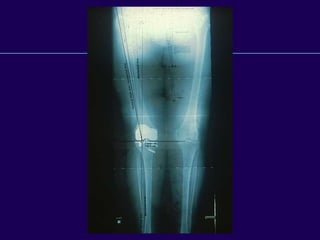

Total Knee Arthroplasty

Radiographic Evaluation

—Standing full length – AP

—Standing AP

—Extension/Flexion laterals

—Tunnel view

—Sunrise view

Weight Bearing X-rays

—Extent of joint space

narrowing

—Ligament stretch out

—Subluxation of femus on tibia